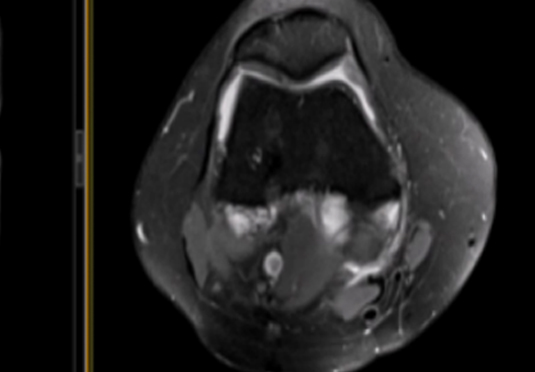

• 微創射頻消融術

適用于微創射頻熱消融術治療患者,引進權威醫療團體輔助引流。

微創射頻消融術